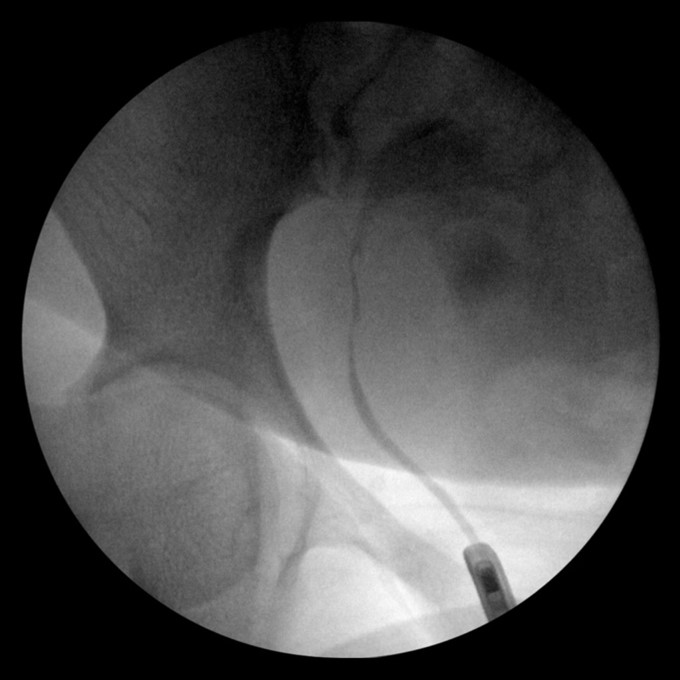

If a urethral injury is suspected, retrograde urethrogram (RUG) is the diagnostic. Contrast is instilled into the urethral meatus, and images are obtained to evaluate for contrast extravasation. The urethra should be placed on stretch during this study with contrast instilled just at the meatus and not via a catheter so that the contrast fills the urethra. A complete disruption is indicated by contrast leaking from the urethra without entering the bladder, while partial tears show partial filling of the bladder. Importantly, a catheter should not be placed before imaging, as blind catheterization can worsen the injury. In patients who already have a Foley catheter, a pericatheter RUG can be performed if there is concern for injury.

Figure 12: Retrograde pyelogram demonstrating contrast extravasation from iatrogenic ureteral injury.